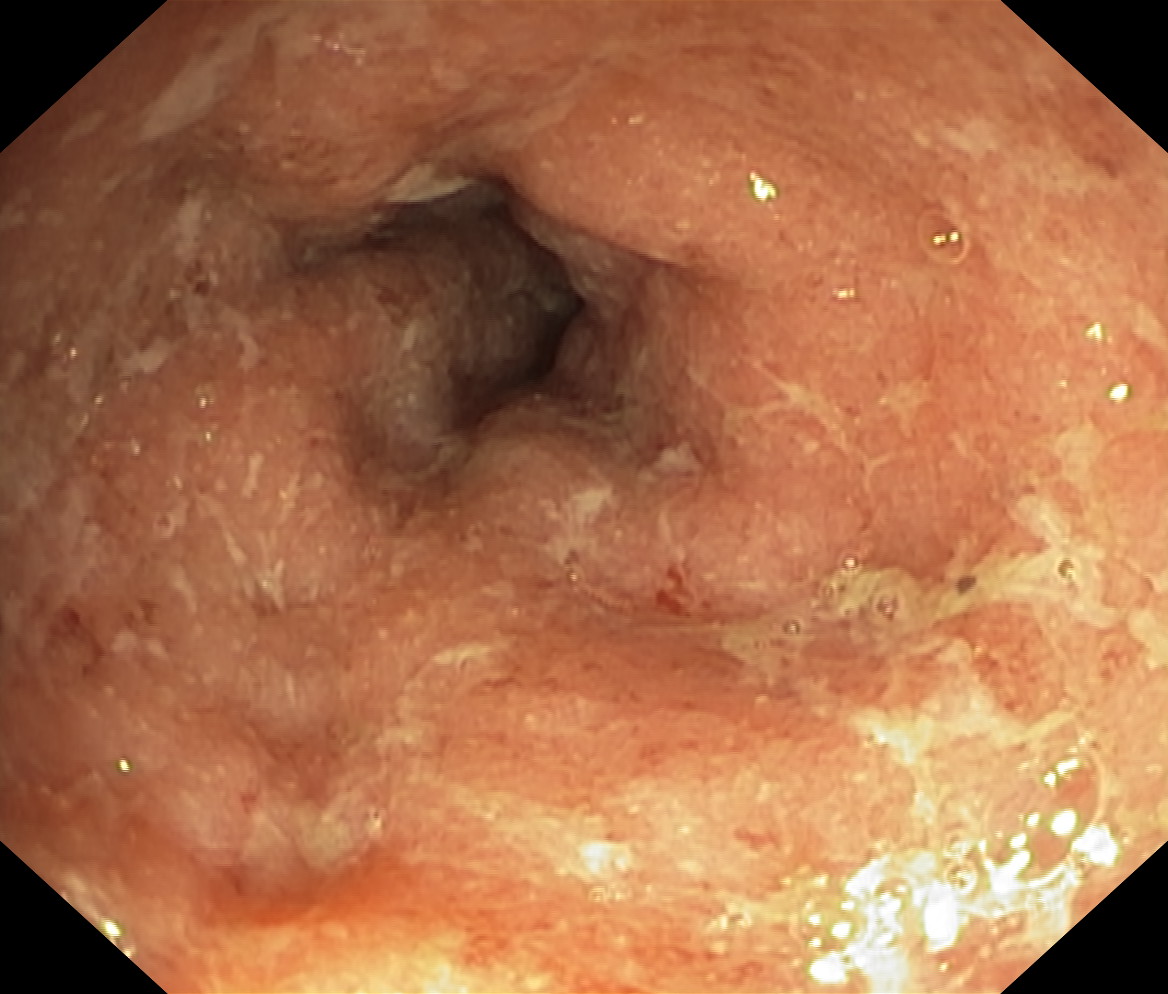

Obrazy endoskopowe

Nowotwory przewodu pokarmowego